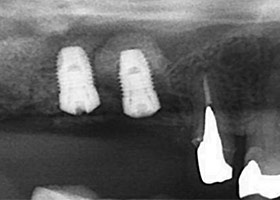

X光片顯示骨頭成功增高

完成時X光片可看見新生骨頭